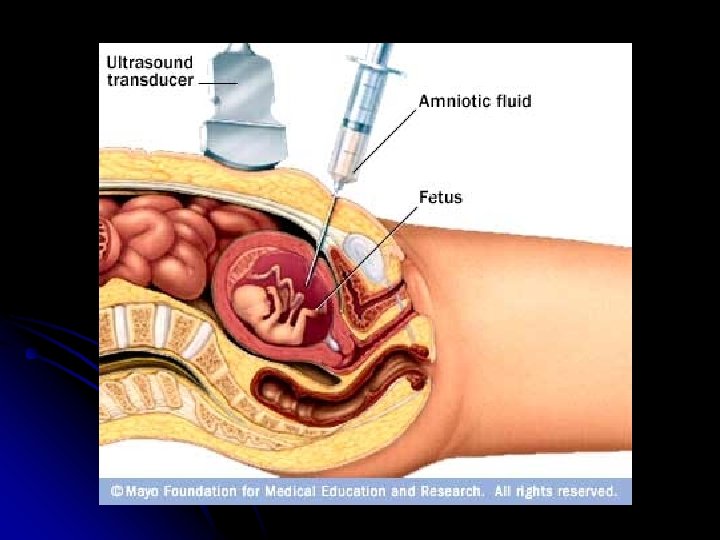

Amniotic fluid spectrophotometer used for: severity of fetal hemolysis

Amniotic fluid spectrophotometer There is excellant correlation between the amount of biliary pigment in amniotic fluid and fetal hematocrit, beginning at 27 weeks’ gestation. -the most common source of bilirubin is tracheal and pulmonary efflux and transudate from the umbilical and placental vessel. -

Other situations might Rh-GAM be used -After induced or spontaneous abortion (50 mg less than 13 wk. of gestation , 300 mg after 13 wk. ) -Ectopic pregnancy (same dosing as for abortion) -Aminocentesis. (300 mg) -percutaneous umbilical blood sampling. -External cephalic version. -Any other case where feto-maternal hemorrhage is suspected.